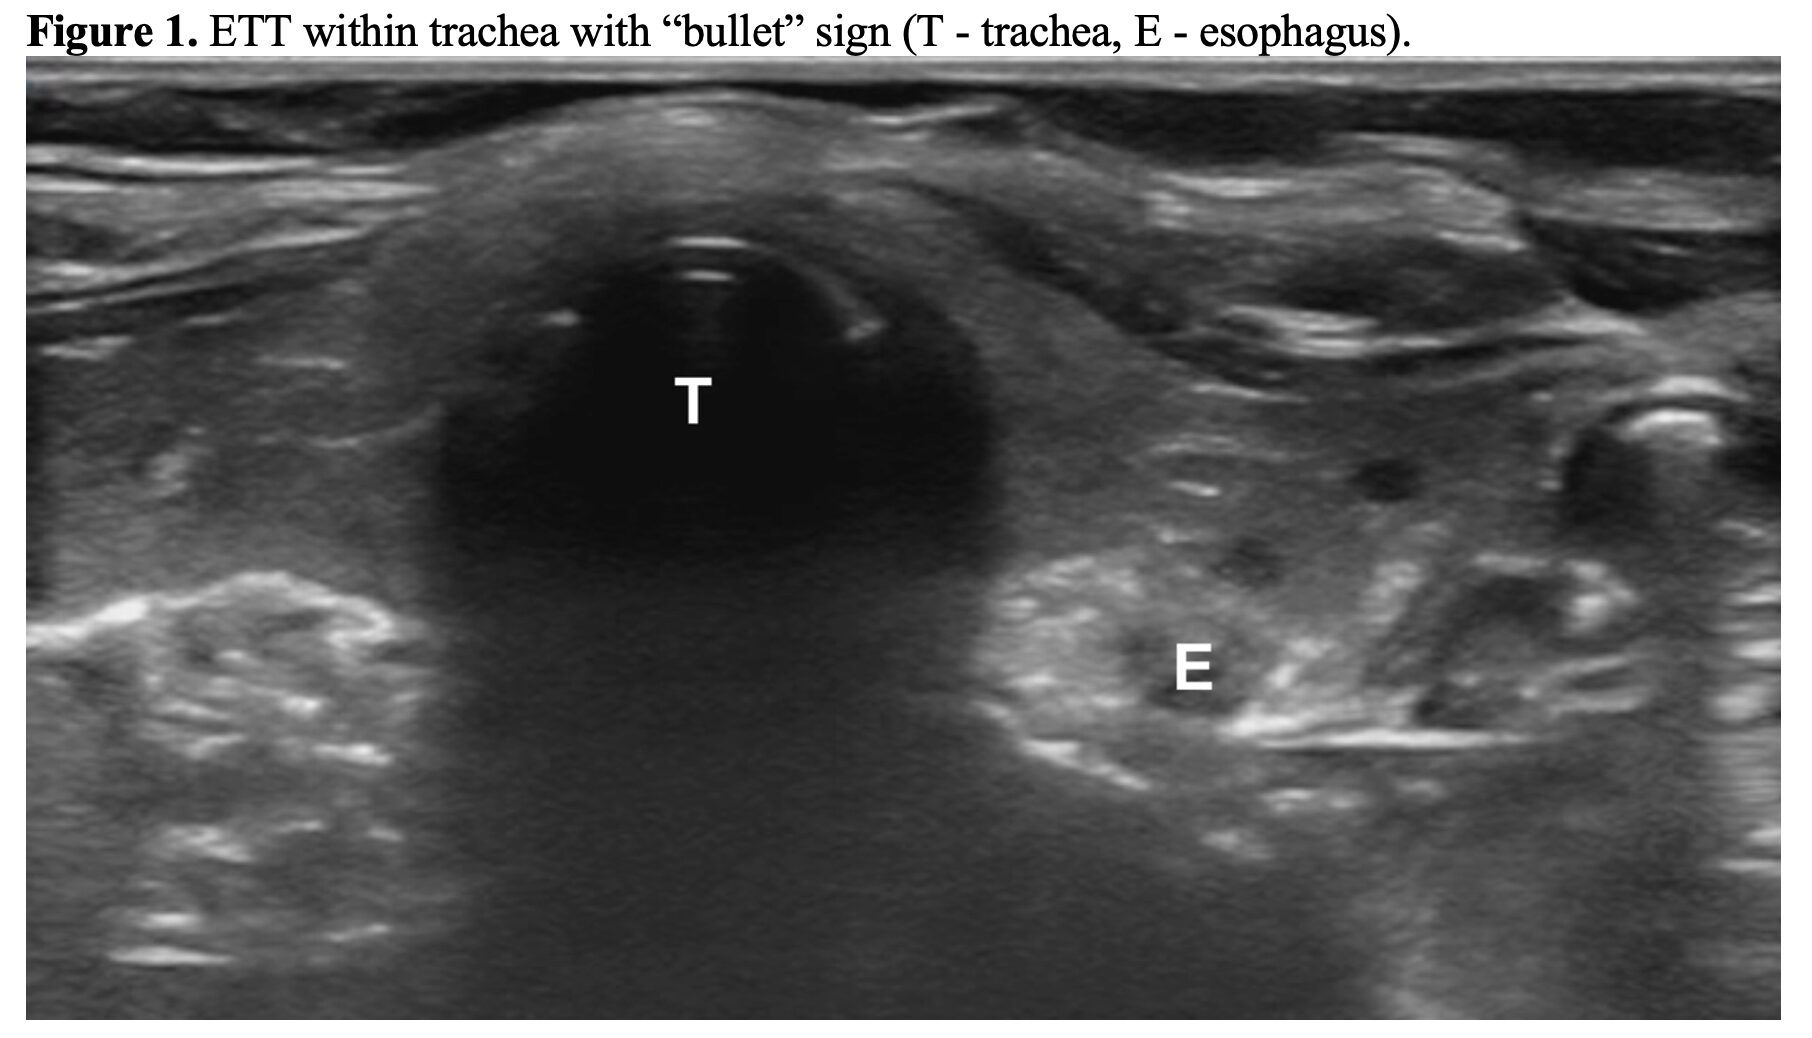

- POCUS: rapid and reliable means of confirming ETT placement within the trachea and looking for mainstem intubation.

- Meta-analysis found POCUS was 99% sensitive and 97% specific for confirming ETT location (109).

- How to do this? Place the linear probe tranversely on the anterior neck at the level of the suprasternal notch (102-106,109-111).

- The static technique can be performed by one clinician after ETI. Looking for a single air-mucosal interface with posterior shadowing (i.e., the “bullet” sign) to confirm ETT placement in the trachea (Figure 1). Twisting of the ETT can help facilitate visualization within the trachea (112,113). If the esophagus is intubated, you’ll see the double tract sign, or a “second” trachea (Figure 2).

- The dynamic method requires another person to evaluate for the presence of motion artifact posterior to the trachea as the ETT passes (confirming appropriate placement), or the appearance of the double tract sign (esophageal placement) (104-106). If it’s not clear, look for bilateral lung sliding (112,114).

- Once the location has been confirmed, may rotate the ultrasound probe 90 degrees clockwise to visualize the ETT cuff in relation to the cricoid and tracheal rings to determine the ETT depth (112,115).